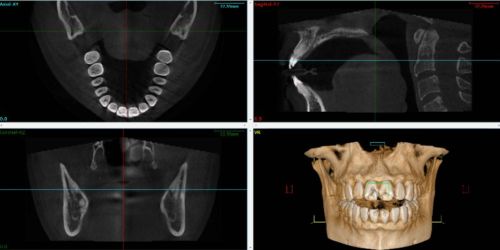

Segmented files are imported after creating the patient file. They are imported as maxillary and mandibular files before or after recording the patient's movements with MODJAW.

NB: before importing the CBCT files, the user must import the patient's 3D files from the intraoral camera.

- Once the file import is complete, the user is able to :

- Replay all recorded motion with CBCT data

- Modulate the appearance and transparency of the CBCT models in the "ADVANCED" module.

- Display the cut view of bone models using the “Cut view” feature

Track the proximity between the condylar head and the glenoid cavity during different movements.

The movements and axiographic tracings are an additional aid to the diagnosis of TMJ disorders as well as in the selection of so-called therapeutic positions.